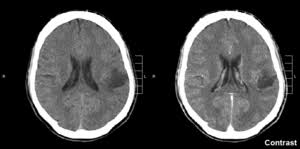

Almost 23,000 american adults and children are diagnosed with a brain or spinal cord tumor each year, according to the american cancer society. Unfortunately, brain cancer is on the rise worldwide, for many reasons. Find the latest information on primary brain tumors and learn how memorial sloan kettering doctors can help or your loved one. Brain cancers fall into two broad categories symptoms of brain tumor. Cancers of the thyroid cancers not linked to obesity dropped 13 percent. Brain tumors on the rise in england, raising cell phone concerns. A cancerous brain tumor is commonly referred to as brain cancer. How brain cancer is treated. More information on the nci web site: Brain cancer can arise from many different types of brain cells (primary brain cancer) or occur when cancer cells type of brain cancer indicates what kind of brain cells that gave rise to the tumor. Brain cancer can change a person's behavior and can be quite deadly. From mild to severe, impacting prognosis (outcomes) depending on the brain cancer type and overall health status of the patient, brain cancer frequently has fair to poor prognosis. It was a low grade tumour (not aggressively malignant), but it was causing pressure on the brain and had to be removed so slabber could reclaim her life.

He was a champion player on the field and has overcome adversity to become a community leader off the field. A cancerous brain tumor is commonly referred to as brain cancer. Depending on which area of the brain is affected, this may cause problems with thinking, acting. Headache is a sign that the tumor is putting pressure on the normal brain and increasing the intracranial pressure, said neurosurgeon dr. Reovirus tends to infect cancer cells and largely leaves healthy cells alone, say researchers. It occurs in the pons area. Until now, there have been few resources to guide brain cancer patients. Except for colon cancer, cancers tied to overweight and obesity increased among those younger than 75. Depending on the brain cancer type and overall health status of the patient, brain cancer frequently. Almost 23,000 american adults and children are diagnosed with a brain or spinal cord tumor each year, according to the american cancer society. The brain cancer survival rate is based on large groups of people, and it cannot be used to predict what will happen to a particular patient. Find out more information about hpv from nhs bradford and airedale. Nearly 1 in 5 new cases in the u.s.

Brain cancer rates are climbing steeply in the united states among people under the age of 45, according to a new study.